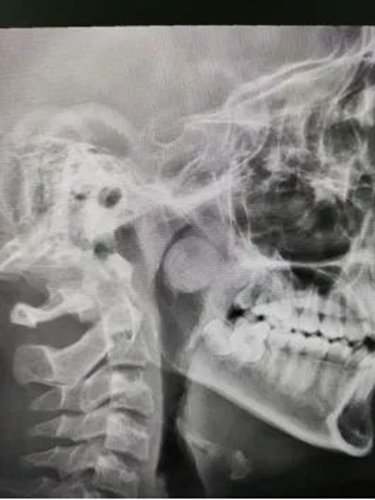

耳鼻喉科接診醫(yī)生查體發(fā)現(xiàn),可可的鼻塞不伴隨打噴嚏和流鼻涕。進(jìn)一步詳細(xì)檢查,結(jié)果顯示,可可的左側(cè)鼻腔后端有一處直徑近2厘米的腫物。腫物不僅堵塞了后鼻孔及鼻咽部,還阻礙了鼻竇的引流,引起了鼻竇炎。

如果不及時(shí)處理,不僅癥狀會(huì)越來(lái)越嚴(yán)重,還可能導(dǎo)致更嚴(yán)重的后果。根據(jù)可可的病情,耳鼻喉科專(zhuān)家決定進(jìn)行手術(shù)治療。

由于兒童鼻腔較成人窄,可操作空間小,耳鼻喉科團(tuán)隊(duì)進(jìn)行了充足的術(shù)前準(zhǔn)備,力爭(zhēng)將手術(shù)風(fēng)險(xiǎn)降到最低。手術(shù)醫(yī)生與麻醉科團(tuán)隊(duì)密切配合,最終通過(guò)內(nèi)鏡引導(dǎo)下在鼻腔內(nèi)切除了腫物。術(shù)后當(dāng)晚,可可就呼吸暢通、不再打鼾了。